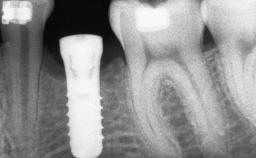

# of Implants 12

Type of Implants One-Piece|Reduced-Diameter

Bone Augmentation Horizontal|Staged

Placement Protocol Early or late implant placement

Bone Volume Deficient horizontally, requiring prior grafting